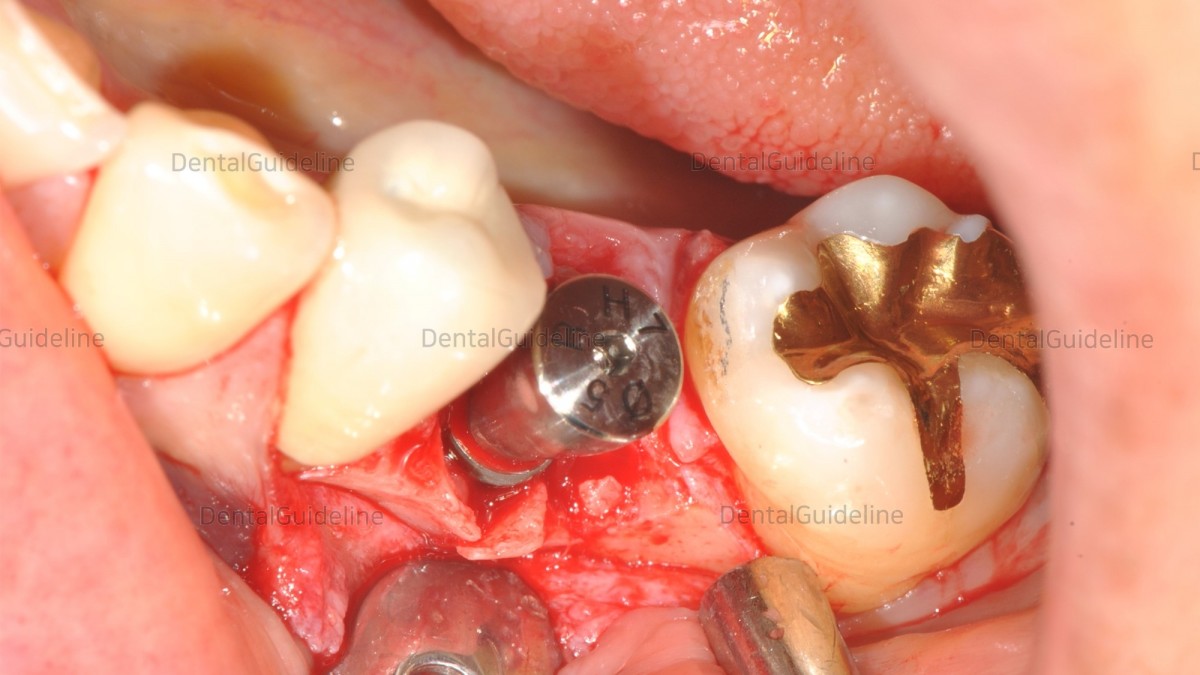

The implant is ready to be inserted. Hiossen(=Osstem) TSIII Ø4.5*L10'

The implant was placed.